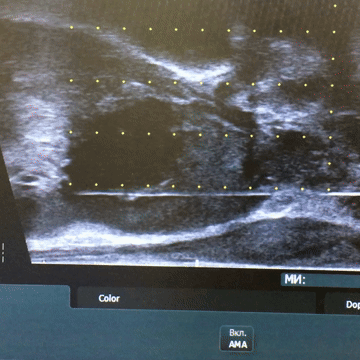

За даними мультипараметричної МРТ було виявлено новоутворення розмірами 12×13×8 мм у лівій частці передміхурової залози, в ділянці верхівки.

За результатами патогістологічного дослідження після 12-точкової біопсії встановлено діагноз: аденокарцинома передміхурової залози, 6 балів за Глісоном (3+3), G1, із ураженням приблизно 25% тканини у трьох біоптатах.

Пацієнту була виконана біполярна фокальна абляція пухлини простати.

Протягом двох років спостереження рівень ПСА знизився з 9 нг/мл до 1,1 нг/мл, що є нормальним показником для пацієнтів цього віку.

За даними контрольного МРТ, проведеного через рік після фокальної терапії, патологічних вогнищ не виявлено.

Повторна біопсія підтвердила наявність чітко окресленої ділянки склерозу в зоні проведеного лікування без ознак злоякісного процесу.